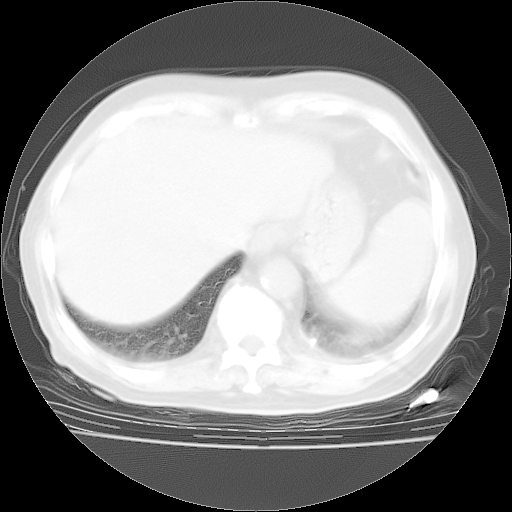

4月28日肺部CT——再次出现类似去年5月9日——透光度降低,“间质性”改变。

4月28日肺部CT——再次出现类似去年5月9日——磨玻璃样、间有“粟粒样”改变。

4月28日肺部CT